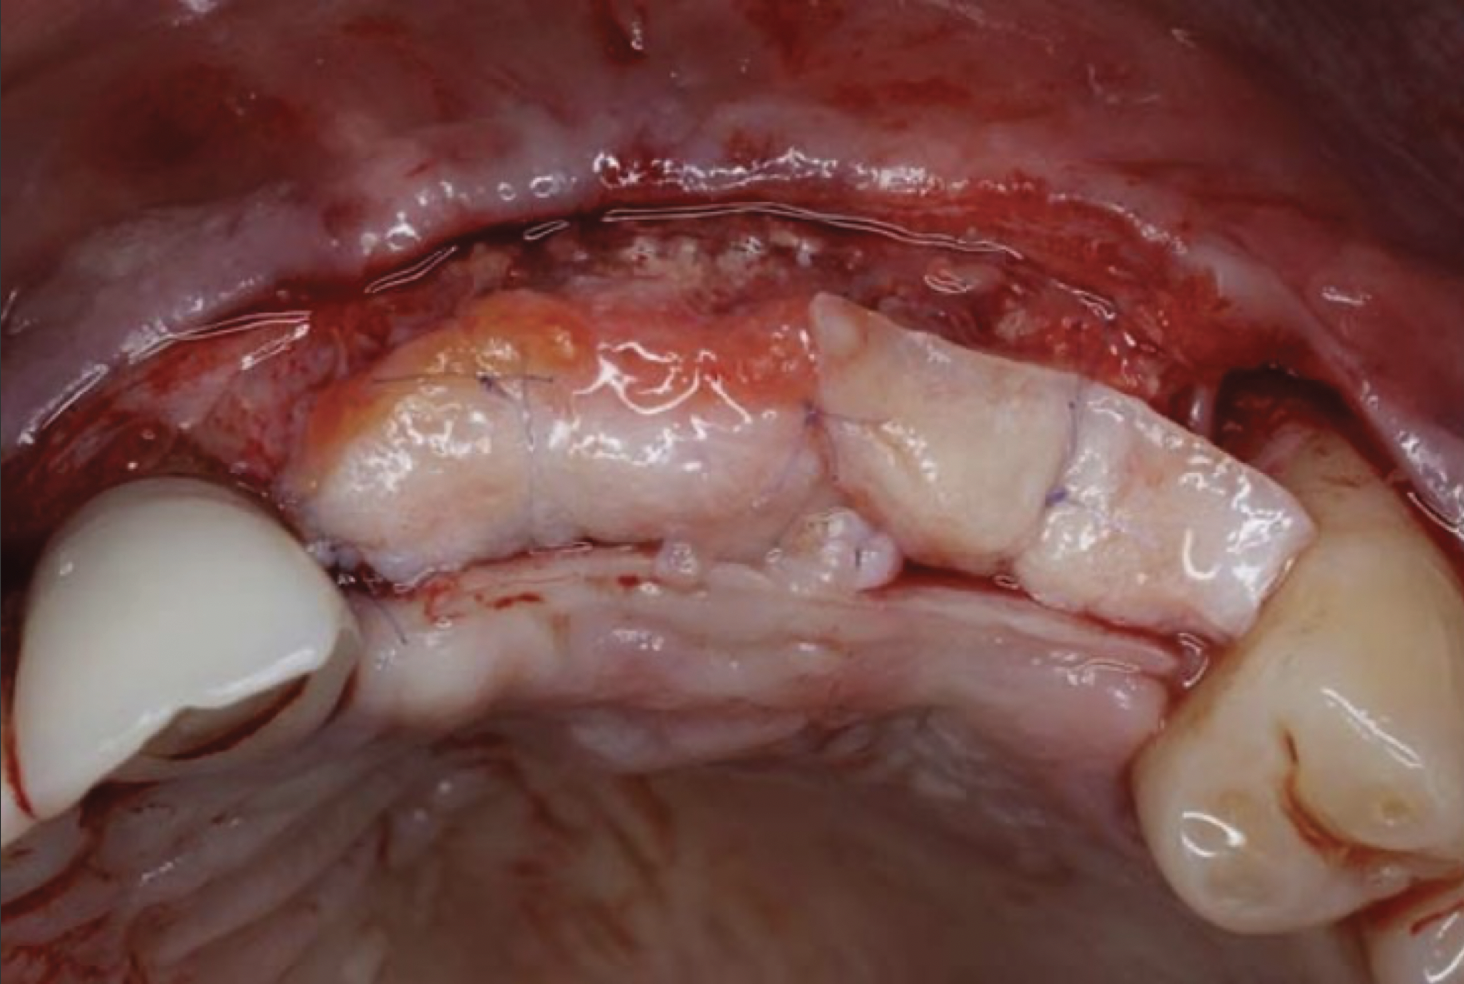

Fig 11. Soft-tissue augmentation with two CTGs.

Figure 11

Fig 12. Two additional CTGs were placed between the implants (ie, the “iceberg” CTG approach).

Figure 12

To enhance the esthetic outcome of the implant therapy, a split-thickness flap was opened at the level of the occlusal and buccal aspects of the implants. Two connective tissue grafts (CTGs) were harvested from the palate and sutured over the implants (Figure 11). Two additional CTGs were also obtained and positioned between the implants to augment the peri-implant papillae. This augmentation technique has been described as the "iceberg" connective tissue graft (iCTG) approach (Figure 12).16 The flap was released and sutured to completely cover the CTGs.